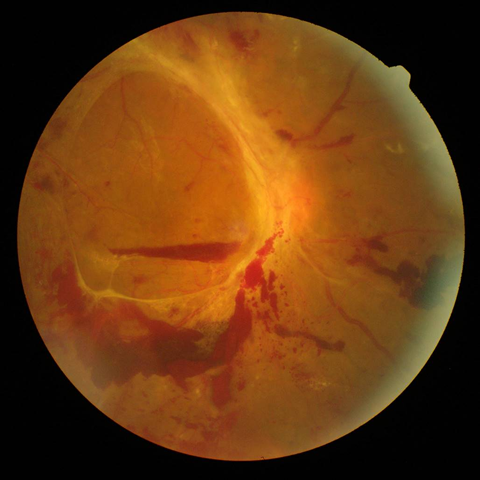

2.前増殖糖尿病網膜症

| 中期の網膜症 | 毛細血管がつまり血管閉塞を生じます。血管閉塞した網膜は虚血におちいり、軟性白斑という所見が生じます。 | 虚血網膜は放置することによって、新生血管が生じ、硝子体出血や増殖膜のもとになるため、この段階で、的確なレーザー治療(網膜光凝固術)をしっかりと行っておくことが非常に重要になります。 |

レーザー光凝固施行前の糖尿病網膜症  レーザー光凝固施行後の糖尿病網膜症 |